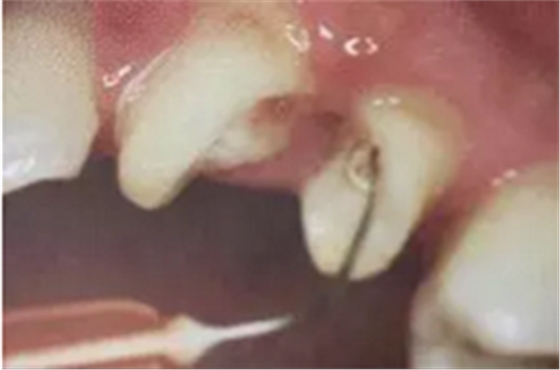

(超聲去除根管殘留物)

通常此時(shí)以超聲潔牙機(jī)更換較細(xì)工作尖進(jìn)入根管(根管消毒沖洗液配合清潔工作后面會(huì)提到),徹底去除樁道根管壁上的附著殘留物,效果明顯。再配合X線片、根管顯微鏡輔助檢查清理的情況下更佳。